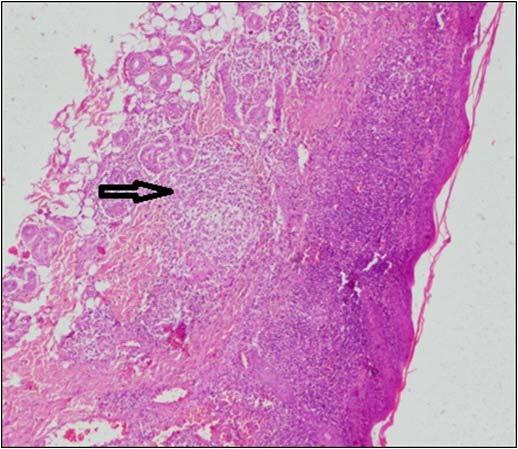

Hypophysitis was diagnosed based on the radiological score proposed by Gutenberg et. al. that showed a sensitivity of 92%, a specificity of 99%, a positive predictive value of 97%, and a negative predictive value of 97% for the diagnosis of autoimmune hypophysitis11. All such patients underwent routine cerebrospinal fluid (CSF) analysis, and estimation of adenosine deaminase (ADA), angiotensin-converting enzyme (ACE), β -human chorionic gonadotropin (hCG) and α-fetoprotein (AFP) in CSF in addition to measurement of serum immunoglobulin G4 (IgG4) level. Idiopathic intracranial hypertension (IIH) was suspected in presence of empty sella (ES), dilated optic nerve sheaths, protrusion of optic nerve papilla into the posterior globes, and compressed ventricles and CSF cisterns on MRI 12

Majority of the patients had abnormal appearances of the HP region on MRI (Table 5) (Figs 1&2). Empty sella with varying thickness of the remaining pituitary tissue was the commonest abnormality noted (28 patients, 52.8% of the cohort). Only 3 patients (5.66%) had apparently normal looking HP region. Hypophysitis was diagnosed retrospectively in 1 lady with ES, whose previous MRI was consistent with hypophysitis11. One male with hypophysitis

Hypophysitis (n=4)

Diffuse enlargement of the pituitary with stalk thickening and rapid, intense, and homogenous contrast enhancement:3; partial empty sella: 1